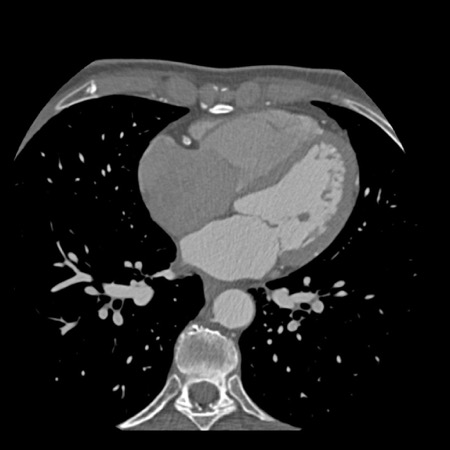

case 3 – Calcium score 0 and severe stenoses.

First, scroll through the CTA images.

How would you describe the findings on the coronary CTA?

The findings are:

- The total calcium

score of 0 indicates the absence of calcified plaque in the coronary

tree. - Severe stenosis

(70-99%) in the mid LAD and D2 branch.